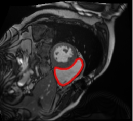

4.3 Comparison with cardic MR images for right ventricle segmentation

Cardiac MRI images often suffer from intensity inhomogeneity due to the varying magnetic susceptibility of cardiac tissues. This can lead to ambiguous boundaries, making it hard for models to consistently identify the left ventricle. Moreover, the heart is composed of several complex anatomical structures, including chambers, valves, and surrounding tissues. Accurately delineating the borders between these various components can be difficult, especially when they are closely positioned or exhibit similar intensity characteristics. In this section, we demonstrate the effectiveness of the RefLSM in segmenting cardiac MR images. The cardiac MR images are standardized to a size of . To enhance the credibility of the proposed model, we segmented 5 cardiac MR images compared the results with 6 other models, including the ALF [MA2019201], LoGRSF [DING2017224], ABC [WENG2021115633], RESLS[8765635], ICTM [WANG2022108794] and FeaACM [XUE2024110673] models. Fig. 5 displays the partial results from all the segmentation models. It is clear that the segmentation results from the RefLSM closely align with the ground truth of the left ventricle segmentation. However, the ALF model demonstrates relatively poor ability to capture the overall structure of the left ventricle; it exhibits limitations with precise boundary detection, particularly in areas of intensity inhomogeneity. Consequently, the evolution curve of the ALF fits into an unstable wave-like result. Suffering from intensity inhomogeneity and surrounding anatomical structures, the LoGRSF model, ABC model and RESLS model all represent over-segmentation and under-segmentation to some extent. Additionally, the results in the 6th column of Fig. 5 show multiple instances where where the ICTM model inaccurately identifies adjacent myocardial tissues as part of the left ventricle due to their similar intensity, leading to false positives. While the FeaACM demonstrates some ability to segment the left ventricle, it is not robust and fails to segment the 5th row of Fig. 5. The 2nd and 3rd rows also include small adjacent excessive regions. In contrast, our proposed model demonstrates marked improvements in accurately capturing the left ventricle’s boundaries. It effectively addresses challenges associated with severe intensity inhomogeneity and noise, resulting in better segmentations. The proposed method appear to maintain better structural integrity in the segmented images, closely aligning with the ground truth.

To quantitatively measure the segmentation results of each model, we compute the Dice and Precision values for left ventricle segmentation. Moreover, we opted for a voilin plot to effectively compare the RefLSM with six other models, as shown in Fig. 7. The results clearly demonstrate that the RefLSM yields superior Dice and Precision values than the other representative models, indicating its closer alignment with the ground truth and highest segmentation accuracy.